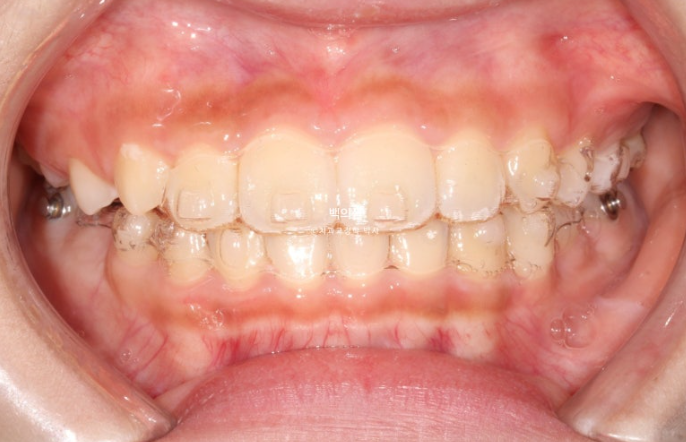

첫 세트의 장치는 총 21개가 나왔습니다.

21개 장치를 다 낀 시점은 6개월 후인 24년 2월입니다.

과개교합은 개선이 되어 아래앞니가 보이고 중심선은 잘 맞습니다.

앞니 뻗침과 돌출은 해결이 되었고 그 사이 남아있던 유치가 여러개 빠졌습니다.

좁았던 악궁이 넓어지면서 모양이 잡혔고